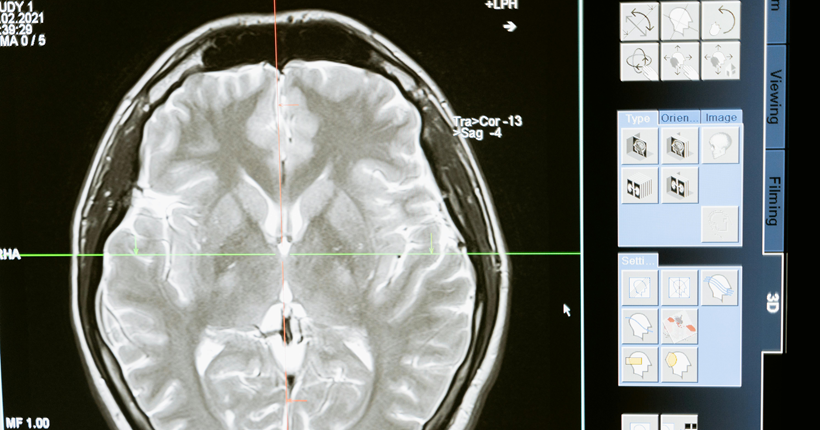

Los principales factores de riesgo encontrados son edad avanzada, menor educación, poca actividad física, hábito de fumar, consumo excesivo de alcohol, hipertensión arterial, diabetes, obesidad, depresión, pérdida o disminución de la audición, aislamiento social, los traumas craneales y la contaminación ambiental. Los biomarcadores fundamentales son: los marcadores que se utilizan en los estudios de neuroimágenes como la tomografía por emisión de positrones (PET) Amiloide, PET tau, PET con fluorodesoxiglucosa (FDG); y en líquido cefaloraquídeo y plasma: Aβ42, Aβ42/Aβ40, p tau 217, p tau 181, proteína gliofibrilar ácida (GFAP), y neurofilamentos de cadena ligeras. Se reconoció el uso de los parámetros cuantificados en el P300 como biomarcadores complementarios clasificadores de la presencia y del nivel de disfunción cognitiva de etiología enfermedad de Alzheimer posible.